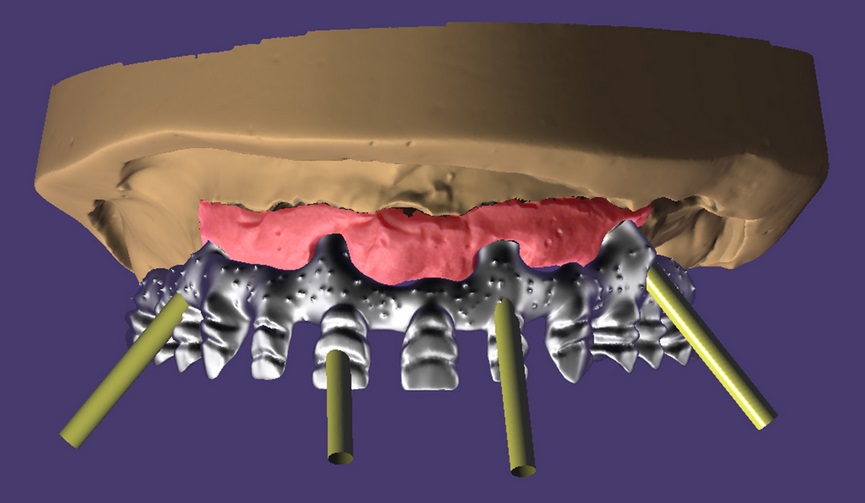

Około 60-letni pacjent zgłosił się do gabinetu lekarza dentysty z protezą całkowitą szczęki górnej, z estetycznym i funkcjonalnym dyskomfortem. Pacjent oczekiwał możliwości przeprowadzenia rehabilitacji, która przywróci prawidłową funkcję zębów i estetyczny uśmiech. Analiza przeprowadzona za pomocą CBCT pozwoliła określić, w jaki sposób struktury kostne pozwolą przygotować i przeprowadzić plan leczenia przy pomocy implantów. Wprowadzono 4 implanty, z których 2 zostały umieszczone w górnym obszarze przednim, a 2 – wychylone odśrodkowo w górnym obszarze przedtrzonowym.

Po 4 miesiącach osseointegracji przeprowadzono drugą fazę chirurgiczną i rozpoczęto zabiegi rehabilitacji protetycznej. Zgodnie [...]